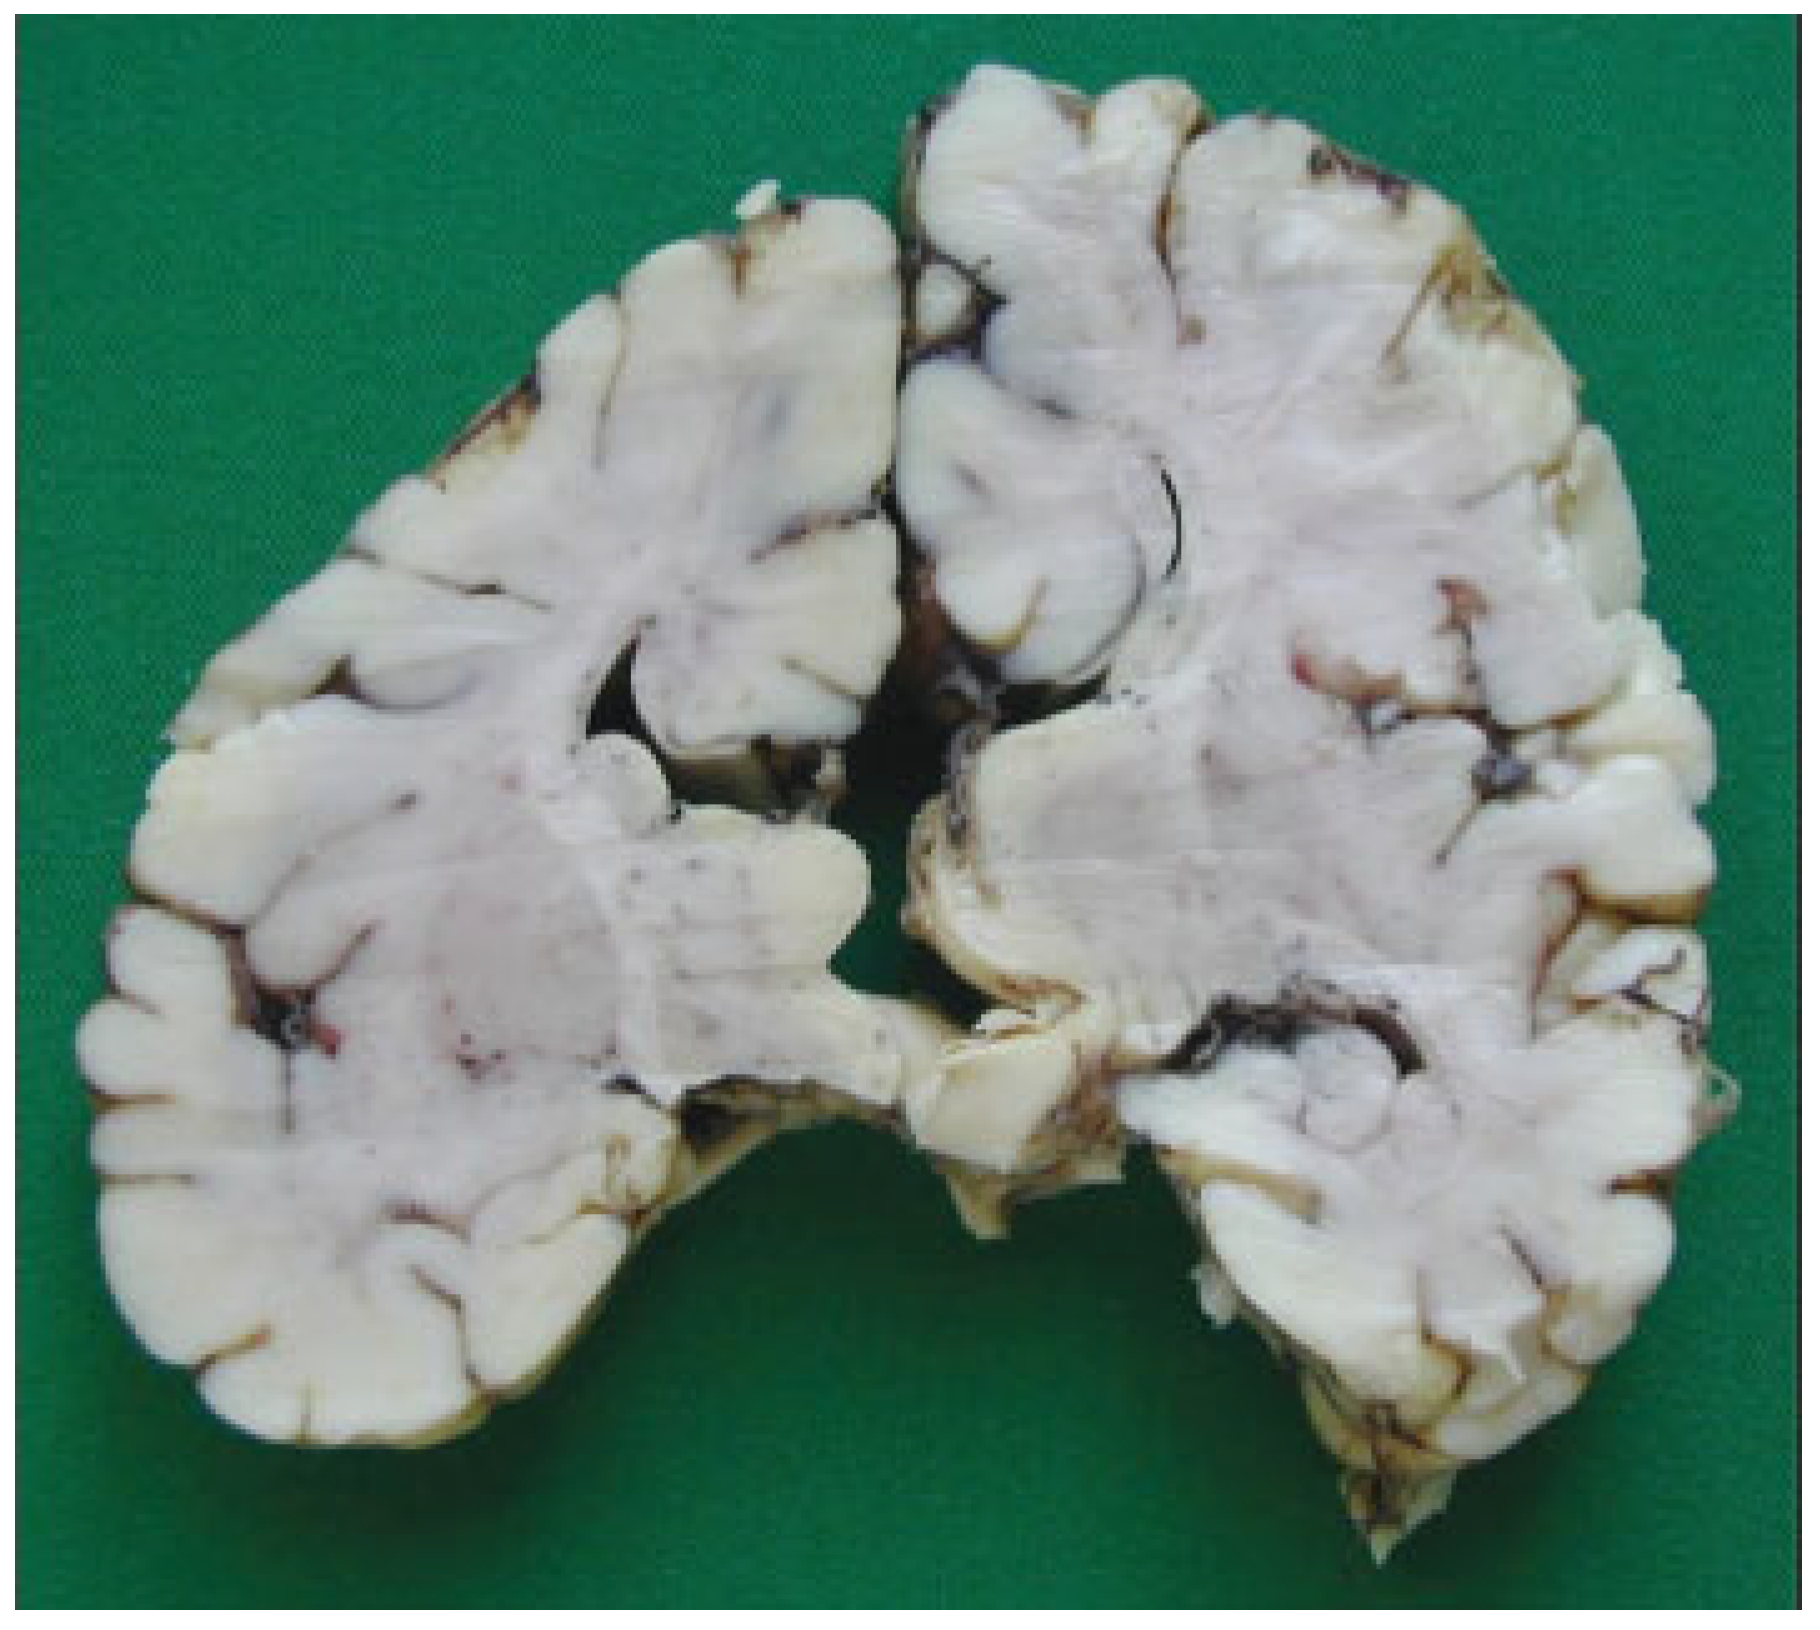

The autopsy study described a girl, 2 months and 20 days old, with karyotype (46,XX). She had frontonasal malformation (hypertelorism, broad nasal bridge, bifid nasal tip and anterior cranium), macrostomia, retrognathia, and bifid tongue. She also presented maxillomandibular bony fusion and fusion of the tongue to the palate and to the inferior lip by a hairy polyp (Figure 8), both corrected surgically. In the cranium, the sella turcica was broadened (Figure 9), with little prominence of the clinoid apophyses and with two cavities that contained two complete hypophyses with two infundibulums (Figure 10). The three cranial fossae were narrowed anteroposteriorly. The central nervous system (CNS) had both olfactory bulbs and corpus callosum agenesis (Figure 11 and Figure 12), anomalous morphology of the brain stem and spinal cord (Figure 13), and neuronal heterotopia in occipital white matter and leptomeningeal heterotopia.

Corpus callosum agenesis.